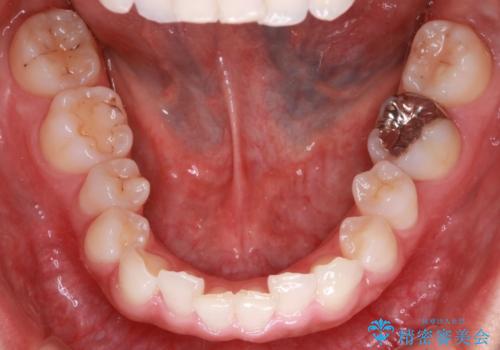

- 前歯のガタガタを主訴に来院されました。

叢生の量は軽度でしたが臼歯の遠心移動を行い、インビザラインにて治療をしました。

叢生の改善に必要なスペースは遠心移動やIPRで作ることが可能です。今回は遠心移動をメインにスペースを作って叢生の改善を行いました。